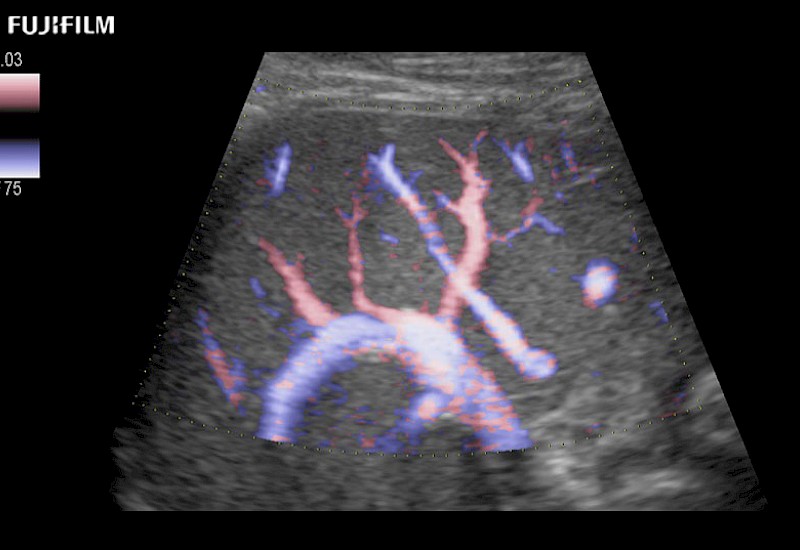

Our dedication to Laparoscopic Surgery allows us to offer superior image quality, outstanding system reliability and intuitive use of cutting edge technology.

The ARIETTA 750 incorporates all of the proven technologies and functions that medical professionals have come to expect from Fujifilm Healthcare.

ARIETTA 750 is the definitive diagnostic ultrasound solution for any clinical setting - Private Office, Imaging Center, or Hospital. The ARIETTA platform provides the ultimate in clinical performance with its state-of-the-art features and large user-friendly display.